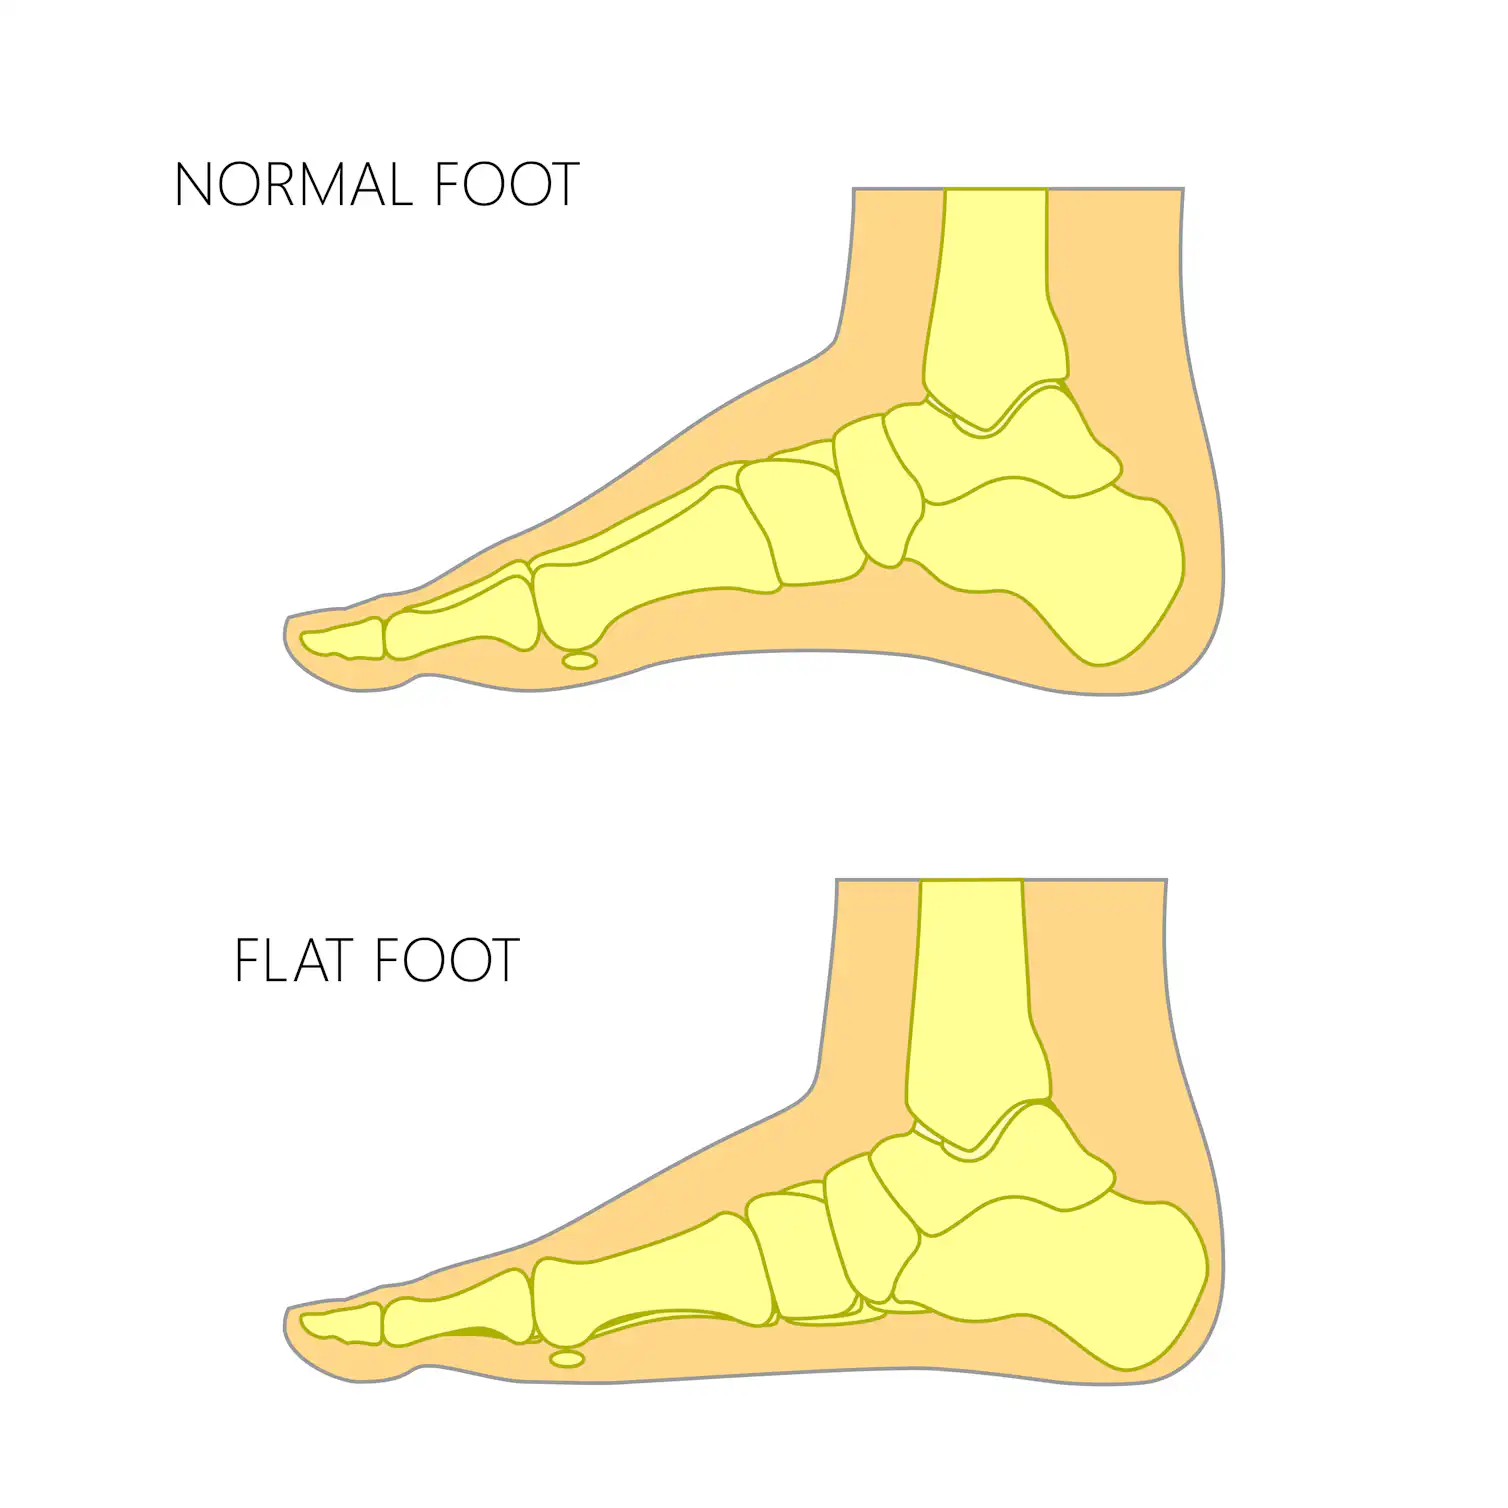

pictures of flat feet

FLAT FOOT- Definition, Symptoms, Causes & Rehabilitation Exercises

Flat Foot: Symptoms, Causes And Treatment Of Pes Planus